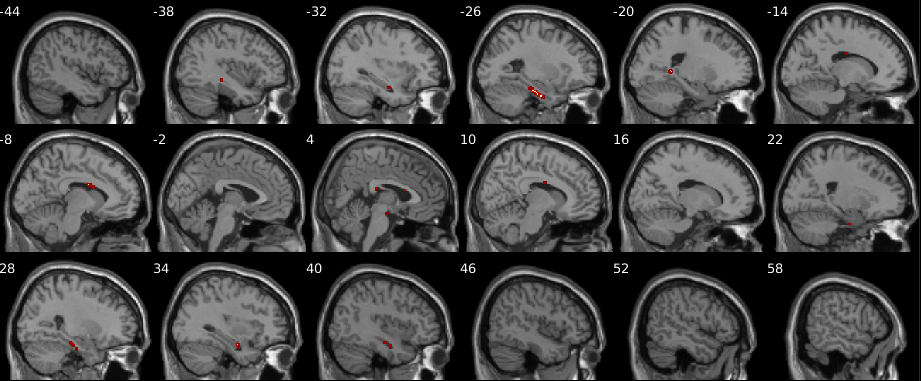

The test statistics obtained using the original data labels whose value exceed the -threshold associated to a given -value will correspond to the null hypothesis rejected. Figure 8 shows the resultant mapping between -threshold and -values for the max null distribution for a given set of hyperparameters. It is evident that the difference across methods is minimal. Moreover, Figure 8 shows that low -values (), which are the main object of interest, show the lowest differences. However, despite the low percent differences between the -values, in the larger datasets (, , and subjects) RapidPT consistently yields slightly more conservative -values near the tails of the distribution. Nonetheless, Figure 11 shows that the resampling risk between RapidPT and the two baselines remains very close to the resampling risk between both baselines. In practice, these plots show that RapidPT will reject the null hypothesis for a slightly lower number of voxels than SnPM or NaivePT.

Despite the slight difference in thresholds, the actual brain regions whose null hypotheses were rejected consistently match between both methods as shown in Figures 9 and 10. Additionally, the regions picked up by both RapidPT and SnPM in Figure 9 correspond to the Hippocampus – which is one of the primary structural brain imaging region that corresponds to the signature of cognitive decay at the onset of Alzheimer’s disease. The regions in Figure 10 contain a subset of the brain regions in Figure 9 which is expected from the thresholds shown in the right column of Figure 7.

ADNI Statistic Maps